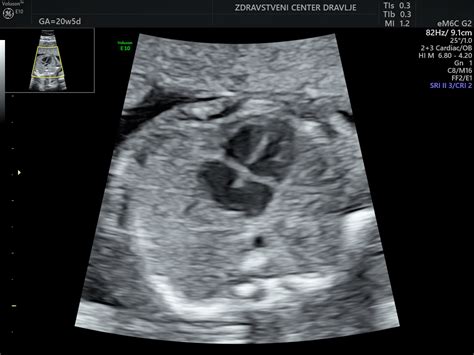

Drugi ultrazvočni pregled (morfologija ploda): Ta ključni pregled se opravi med 20. in 24. tednom nosečnosti. Med njim se zelo natančno preveri razvoj vseh organskih sistemov ploda. Posebna pozornost je namenjena srcu in velikim žilam, ki iz njega izhajajo, saj lahko na ta način odkrijemo morebitne strukturne nepravilnosti v razvoju srca, prebavnega sistema, živčevja ali mišično-kostnega sistema. Poleg tega se med tem pregledom določi trenutna lega ploda, oceni posteljica, popkovnica, količina plodovnice ter izračuna ocenjena telesna teža ploda.